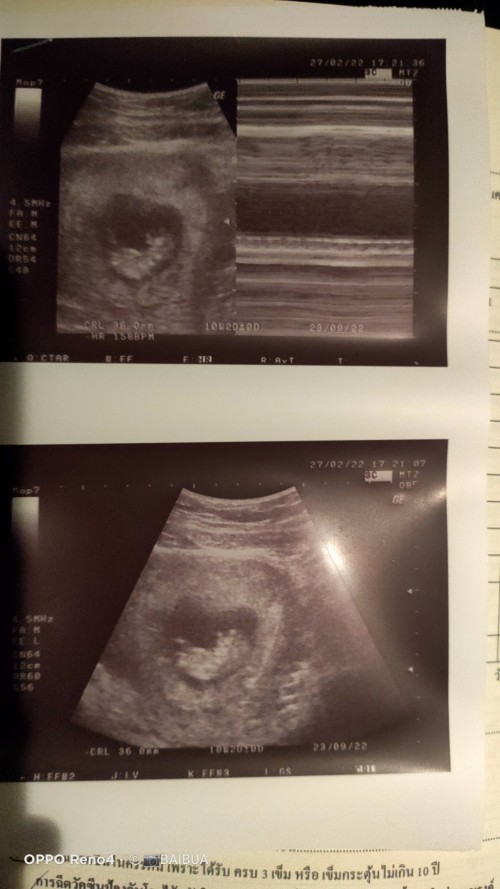

ของเราเห็นน้องตอน10วีคคะ ตอนนั้นน้องยาวแค่3ซม.เอง 🥰🥰